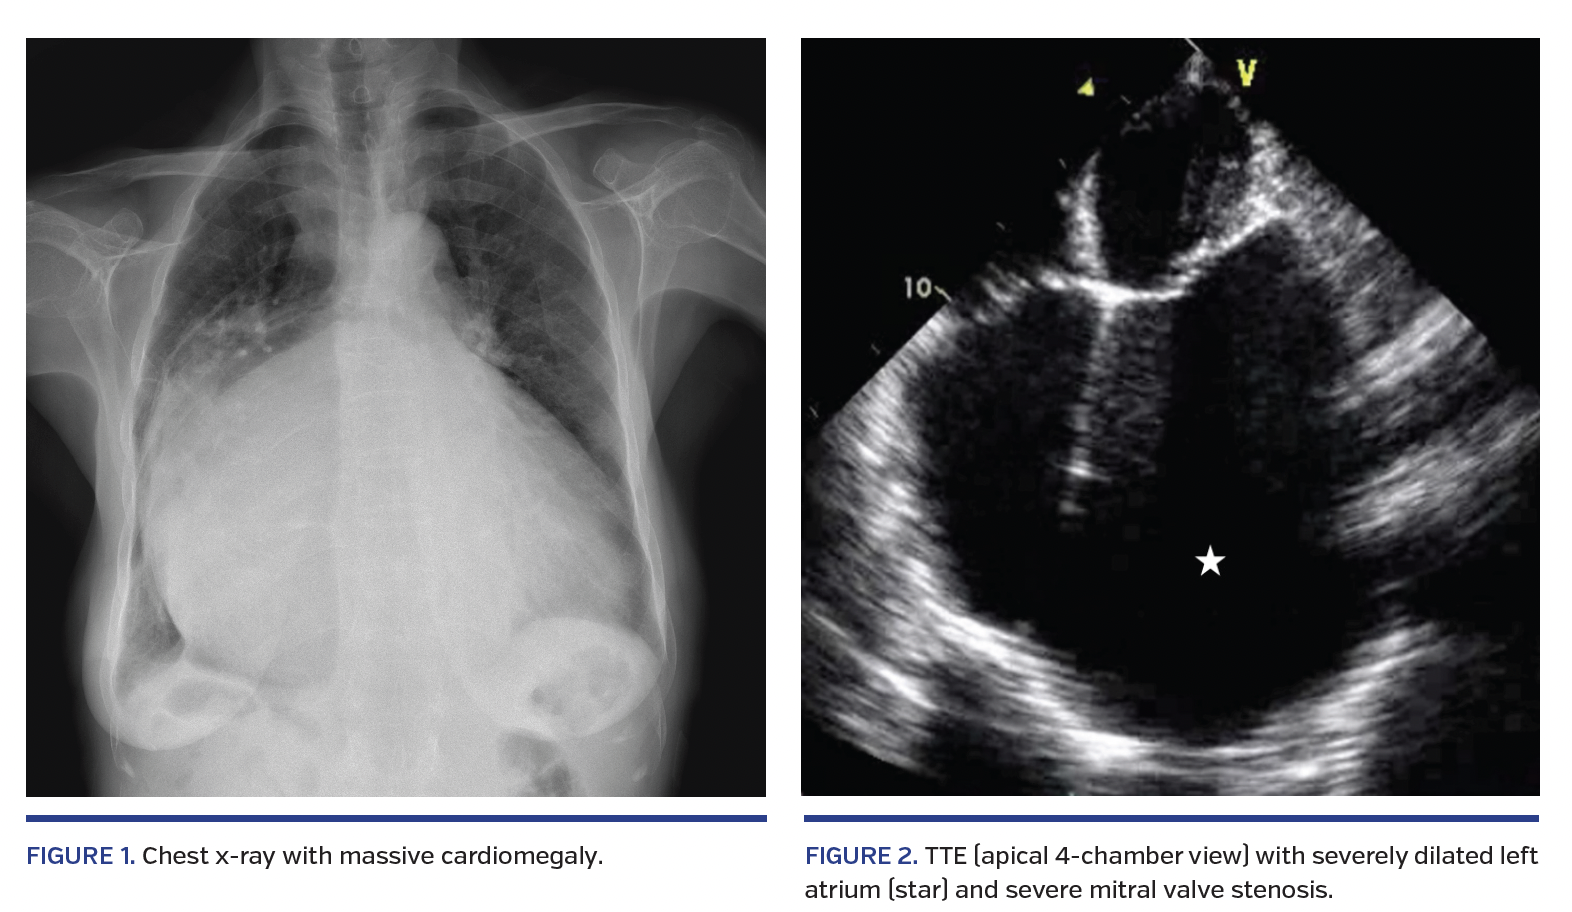

Chest x-ray showed marked cardiomegaly with pulmonary edema and no evidence of chest wall deformity (Figure 1). Atrial fibrillation was noted on electrocardiogram without significant ischemic changes. She responded to intravenous diuretics, which improved her CHF symptoms. Transthoracic echocardiogram demonstrated rheumatic mitral valve disease with severe stenosis (valve area 0.9, cm2), moderate to severe mitral regurgitation and a massively dilated left atrium (Figure 2). There was also severe tricuspid regurgitation with a reduced left ventricular (LV) ejection fraction of 50%. Left atrial diameter was 8.8 cm and LV end-diastolic diameter was 6.7 cm.